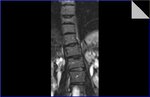

Ein Foto meiner "inneren Schönheit" hab ich mal angehängt.

Ein Foto meiner "inneren Schönheit" hab ich mal angehängt.